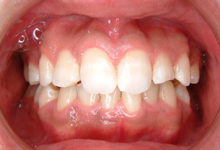

2か月後です。反対咬合は治っています。現在は正常な噛み合せになりました。

これからまだ永久歯に生え替わるので、注意深く定期的に観察していきます。生え替わった後に、また反対咬合になりこともあります。